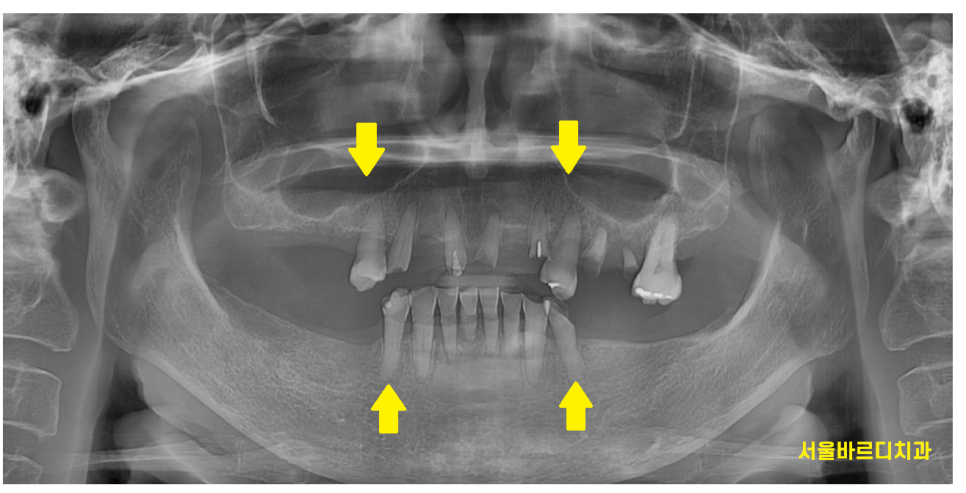

23.09.02

이미 어금니 상실이 많은 상황에서는

치료 방안이 크게 틀니와 임플란트 치료로 나누어집니다.

두개 치료의 선택지의 장,단점 비교를 충분히 해드리고

선택은 환자분께서 해주시는거지만

이 상황에서 단 1개의 자연치라도 더 살리는 것은

앞으로의 치료 방향에 중요한 결정이됩니다.

그래서 치아 뿌리 상태를 확인하는

작은 x-ray도 찍고

평가하였습니다.

23.10.18

보험 임플란트 2개 사용이 가능해서

2개는 보험 임플란트로

나머지 11개까지 합해서

총 13개의 강동구 임플란트

하루에 다 식립해드렸습니다.